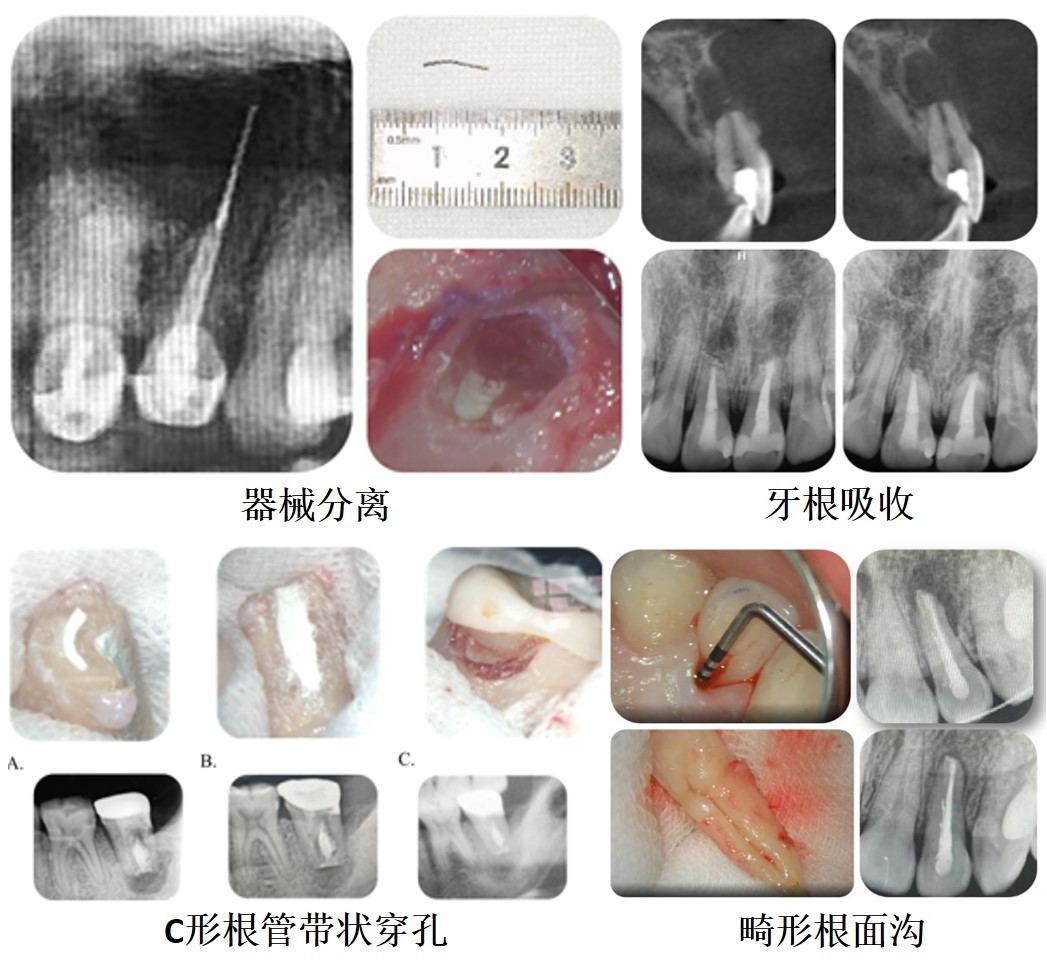

1. 根管治疗或再治疗失败:如桩冠修复的患牙根管充填不严密、遗漏感染侧支根管。

3. 根尖吸收或穿孔:外伤或不当操作导致牙根受损。